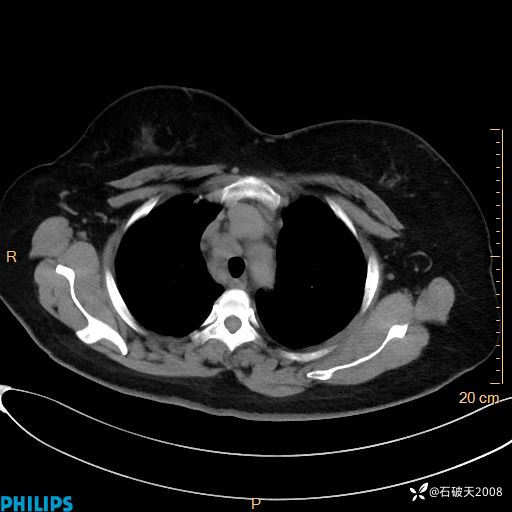

纵隔窗